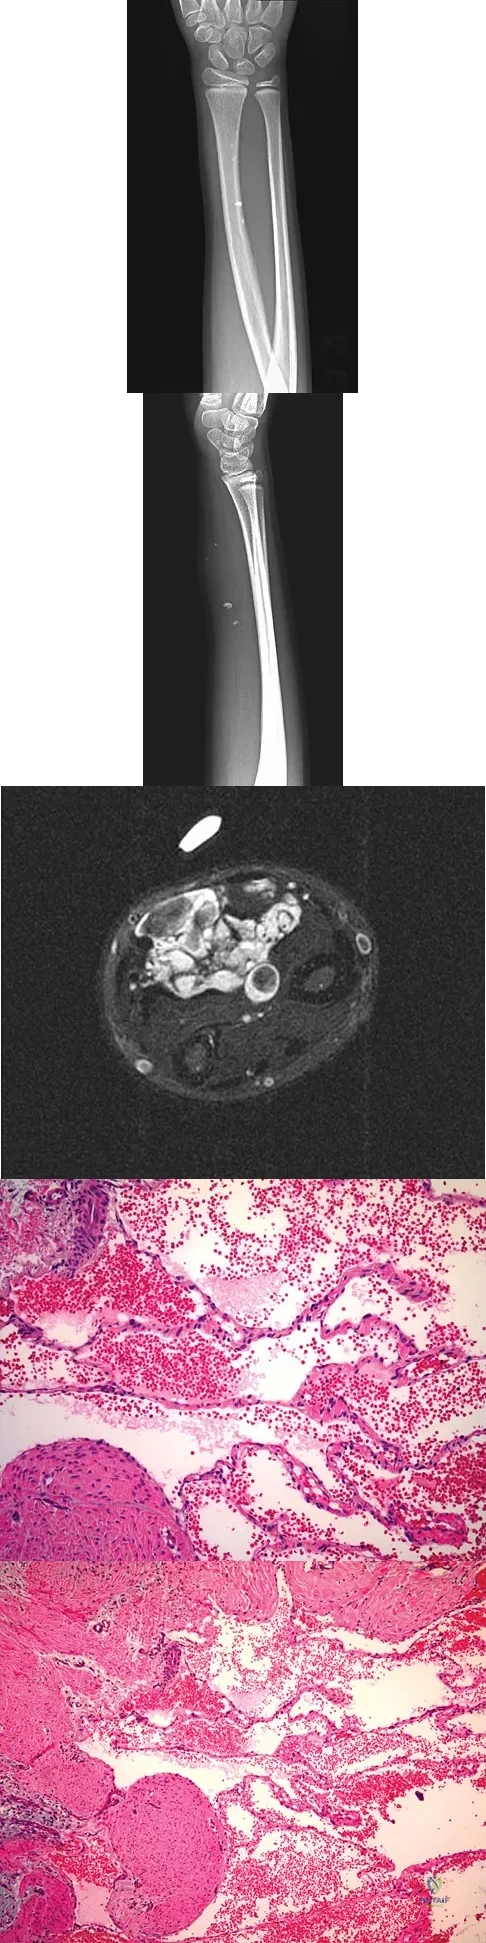

A 7-year-old girl has had a painful forearm for the past 2 months. Examination reveals fullness on the volar aspect of the forearm. Radiographs and an MRI scan are shown in Figures 42a through 42c. Biopsy specimens are shown in Figures 42d and 42e. What is the most likely diagnosis?

Explanation